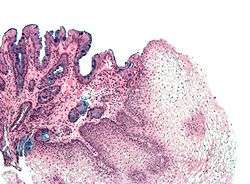

Intestinal metaplasia

The presence of goblet cells, called intestinal metaplasia, is necessary to make a diagnosis of Barrett's esophagus. This frequently occurs in the presence of other metaplastic columnar cells, but only the presence of goblet cells is diagnostic. The metaplasia is grossly visible through a gastroscope, but biopsy specimens must be examined under a microscope to determine whether cells are gastric or colonic in nature. Colonic metaplasia is usually identified by finding goblet cells in the epithelium and is necessary for the true diagnosis.

Many histologic mimics of Barrett's esophagus are known (i.e. goblet cells occurring in the transitional epithelium of normal esophageal submucosal gland ducts, "pseudogoblet cells" in which abundant foveolar (gastric) type mucin simulates the acid mucin true goblet cells). Assessment of relationship to submucosal glands and transitional-type epithelium with examination of multiple levels through the tissue may allow the pathologist to reliably distinguish between goblet cells of submucosal gland ducts and true Barrett's esophagus (specialized columnar metaplasia). Use of the histochemical stain Alcian blue pH 2.5 is also frequently used to distinguish true intestinal-type mucins from their histologic mimics. Recently, immunohistochemical analysis with antibodies to CDX-2 (specific for mid and hindgut intestinal derivation) has also been used to identify true intestinal-type metaplastic cells. The protein AGR2 is elevated in Barrett's esophagus,[11] and can be used as a biomarker for distinguishing Barrett epithelium from normal esophageal epithelium.[12]